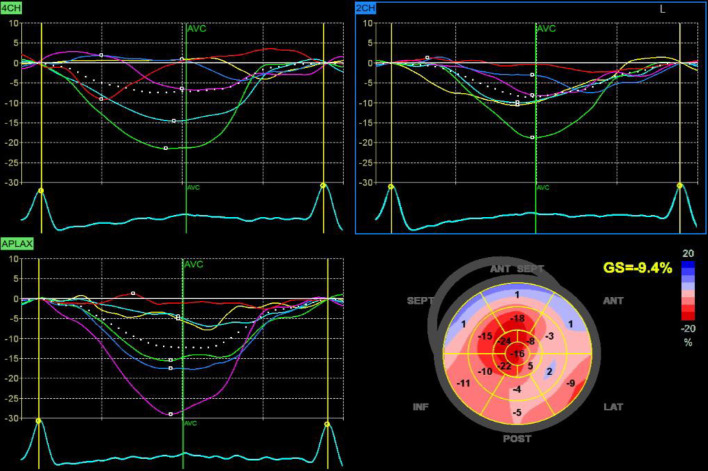

Results: By 2D echocardiography, patient group revealed significantly lower all LA functions vs. control group including reservoir (26 ± 4 vs. 43 ± 3, P < 0.001), conduit (-14 ± 2 vs. -25 ± 2, P < 0.001), and booster pump functions (-12 ± 2 vs. -18 ± 1, P < 0.001). PAP was significantly higher in patient group (42 ± 7 vs. 27 ± 4 in control group). LVGLS was significantly lower in patient group (-15±1.4% vs. -23±2% in control group). Using 3D speckle tracking echocardiography (STE), there were a significantly higher indexed maximum LA volume (Vmax indexed) (43.5 ± 5.6 vs. 28.7 ± 3.7, P < 0.001), but significantly lower left atrial strain at reservoir function (LASr) (24 ± 4 vs. 41 ± 3, P < 0.001), left atrial strain at conduit function (LAScd) (-13 ± 2 vs. -24 ± 2, P < 0.001), and left atrial strain at contractile function (LASct) (-11 ± 2 vs. -18 ± 1, P < 0.001).

Abstract Image